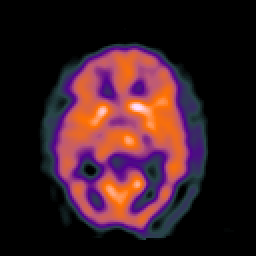

SPECT TC Study #2 -- Slice #27

[Home][Help][Clinical][Tour 1][Tour 2][Tour 3] Slice 27